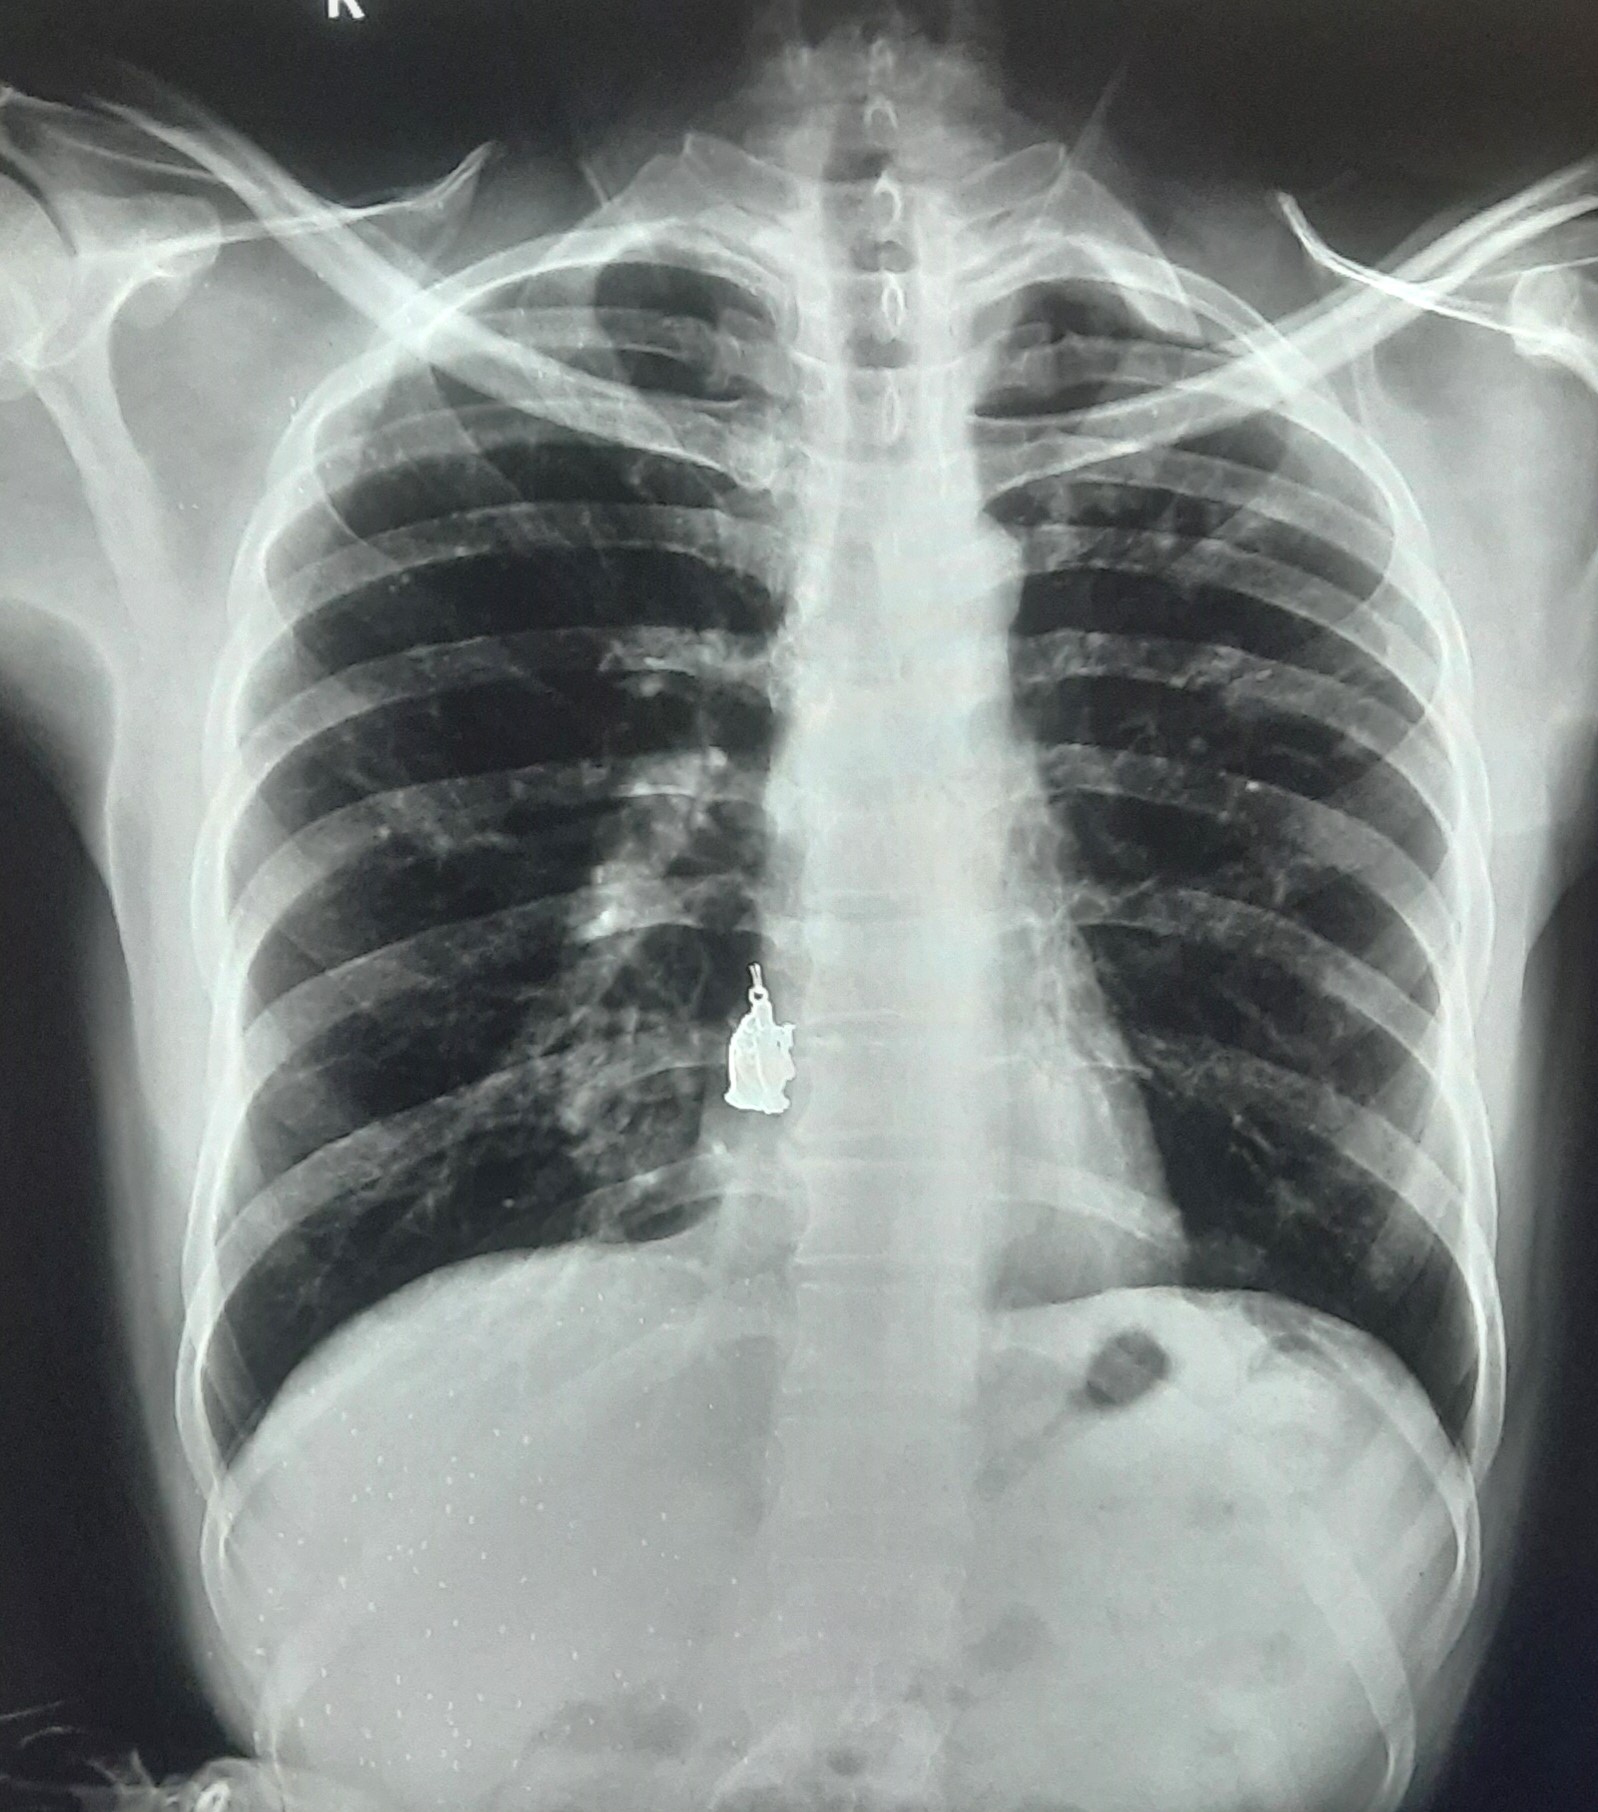

| IGGMC, Nagpur | 29-4228 | IGGMC, Nagpur | Parasnath Tiwari | Pulmonary Tuberculosis In Childhood Took ATT 6 Month |

| Chest X-Ray Image |